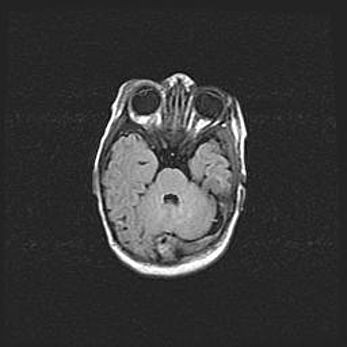

Подострая гематома правой гемисферы мозжечка.

Наружная гидроцефалия.

Возраст: 15 дней

Вес: 3100 г

Пол: женский

Окружность головы: 37 см

Срок гестации: 35-36 недель

При открытой наружной форме гидроцефалии у новорожденных расширяются и переполняются субарахноидные пространства.

Кровоизлияния в мозжечок имеют две клинико-анатомические формы: полушарные гематомы и кровоизлияния в червь.

К появлению этой патологии может привести: повреждения головного мозга, возникающие в результате асфиксии и гипоксии плода при беременности, или травмы во время родов. Редко гематома мозжечка может быть результатом первичной коагулопатии и сосудистой мальформации, диссеминированном внутрисосудистом свертывании, изоиммунной тромбоцитопении.